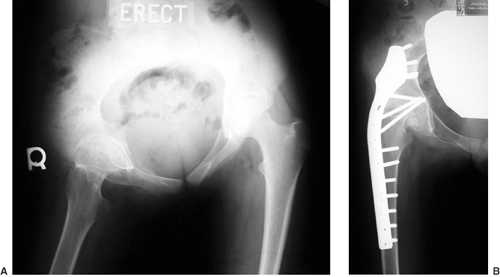

Figure 27.15 The anteroposterior pelvic radiographs of an 8-year-old child with developmental coxa vara. A: Preoperative radiograph. B:

The postoperative radiograph 11 months after the subtrochanteric proximal femoral derotational osteotomy and fixation with a sliding hip screw demonstrates spontaneous closure of the proximal femoral epiphyseal plate. The greater trochanteric apophyses remain open. (Courtesy of Perry L. Schoenecker.) |